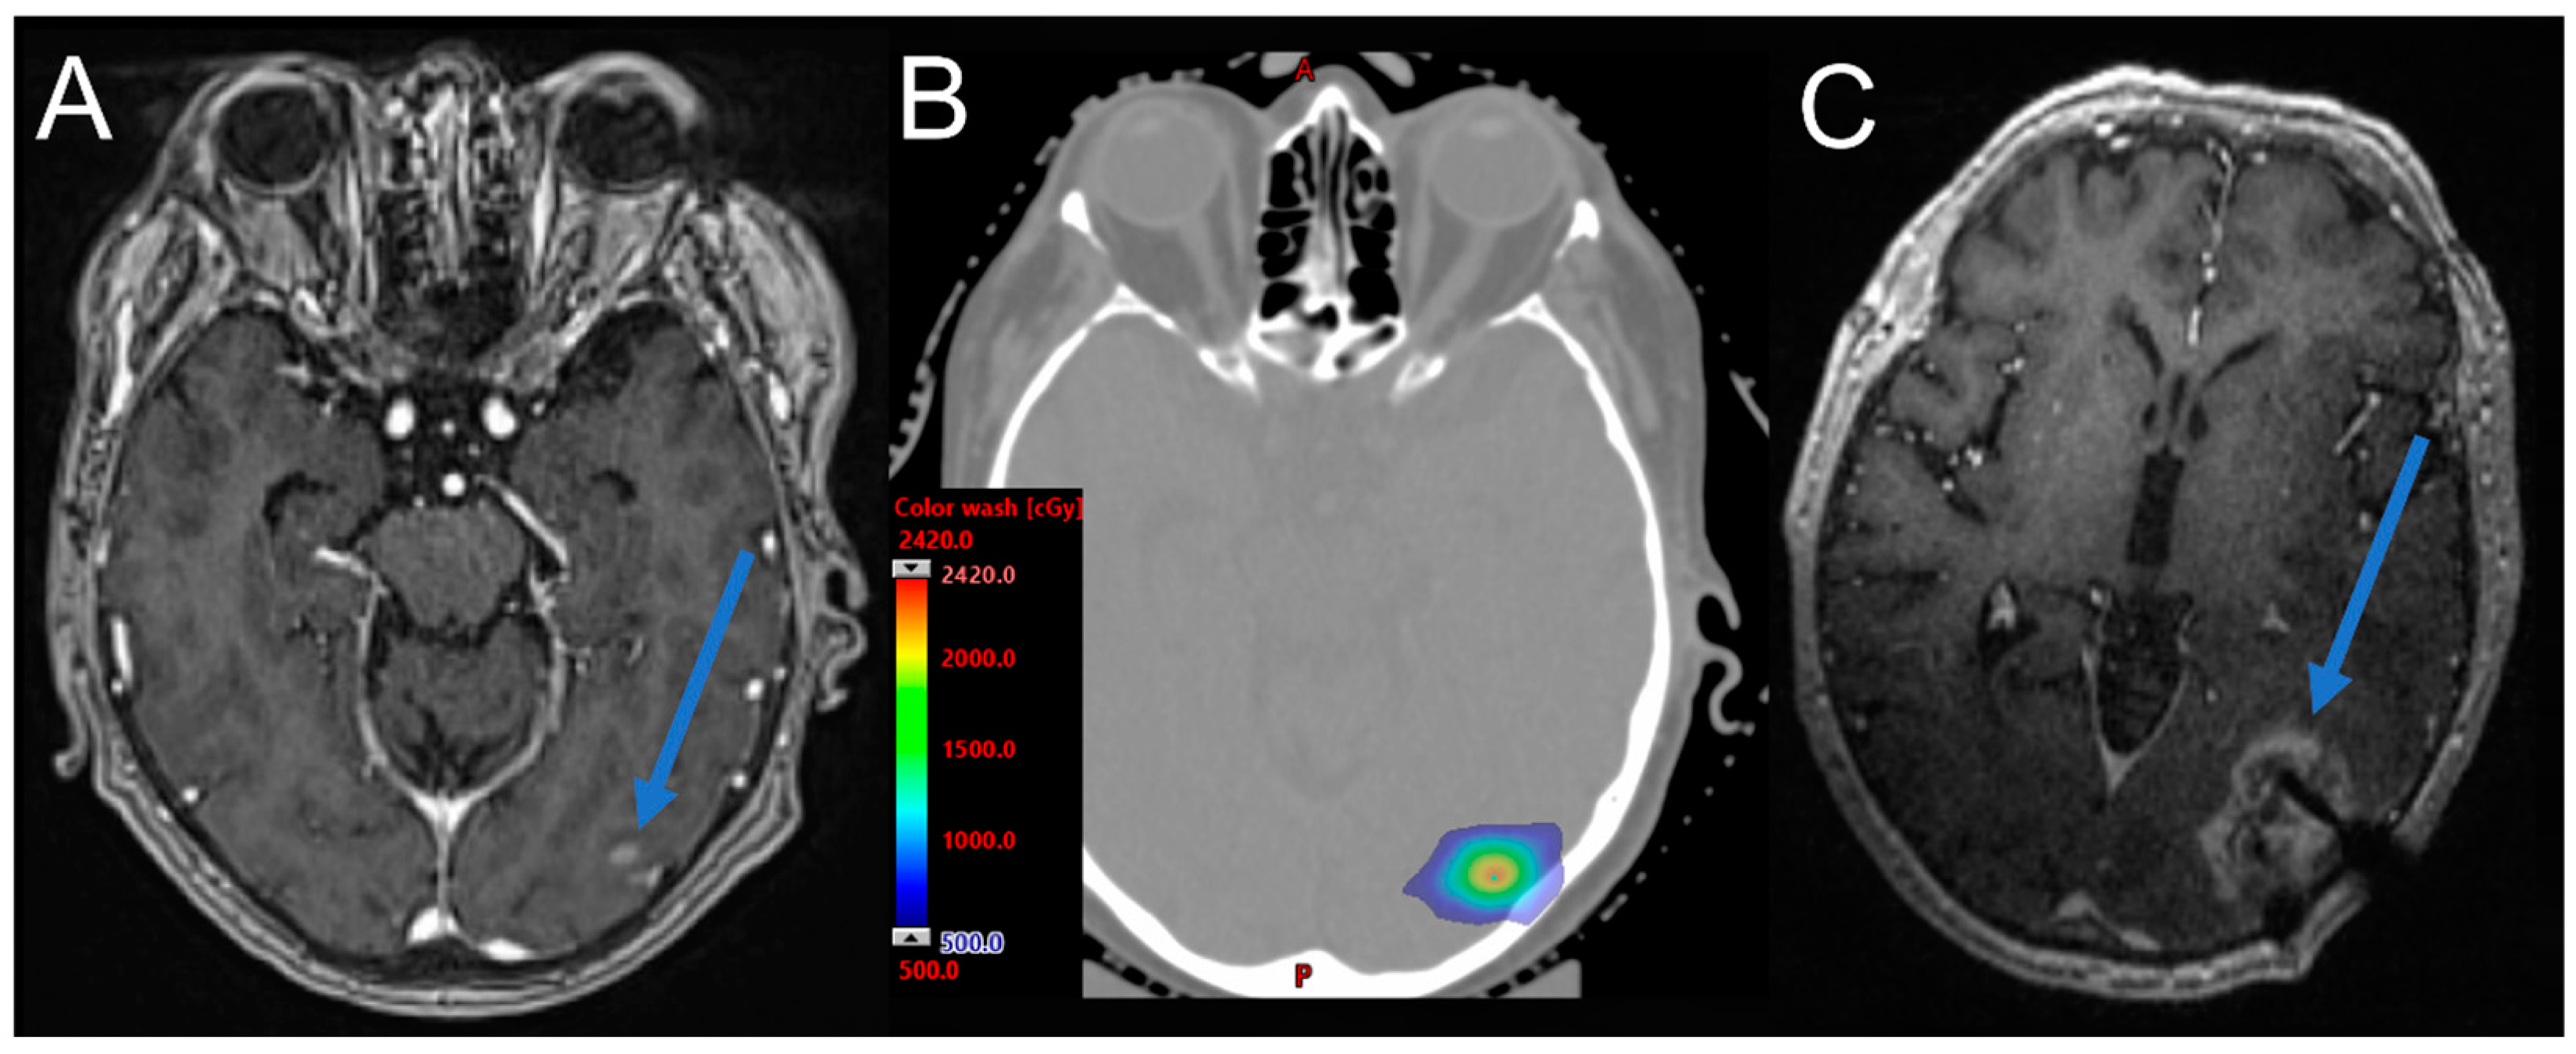

7.1. Dosimetric Strategies